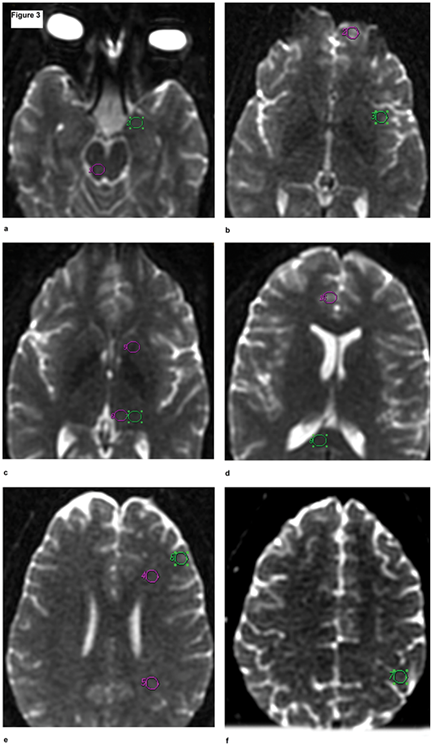

Compararon mediante neuroimagen

cerebros de meditadores Zen

de larga duración

(más de 10 años con una media

de una hora de meditación al día)

con los de personas sanas de la

misma edad y sexo que no meditan.

Se pudo observar que los meditadores Zen

presentan niveles de glutamato, el principal

neurotransmisor excitatorio del sistema

nervioso central, significativamente

más bajos que los

no meditadores.

Esto podría explicar los

menores niveles de depresión,

dolor y mejor capacidad de atención,

memoria y concentración que se

observan en meditadores.